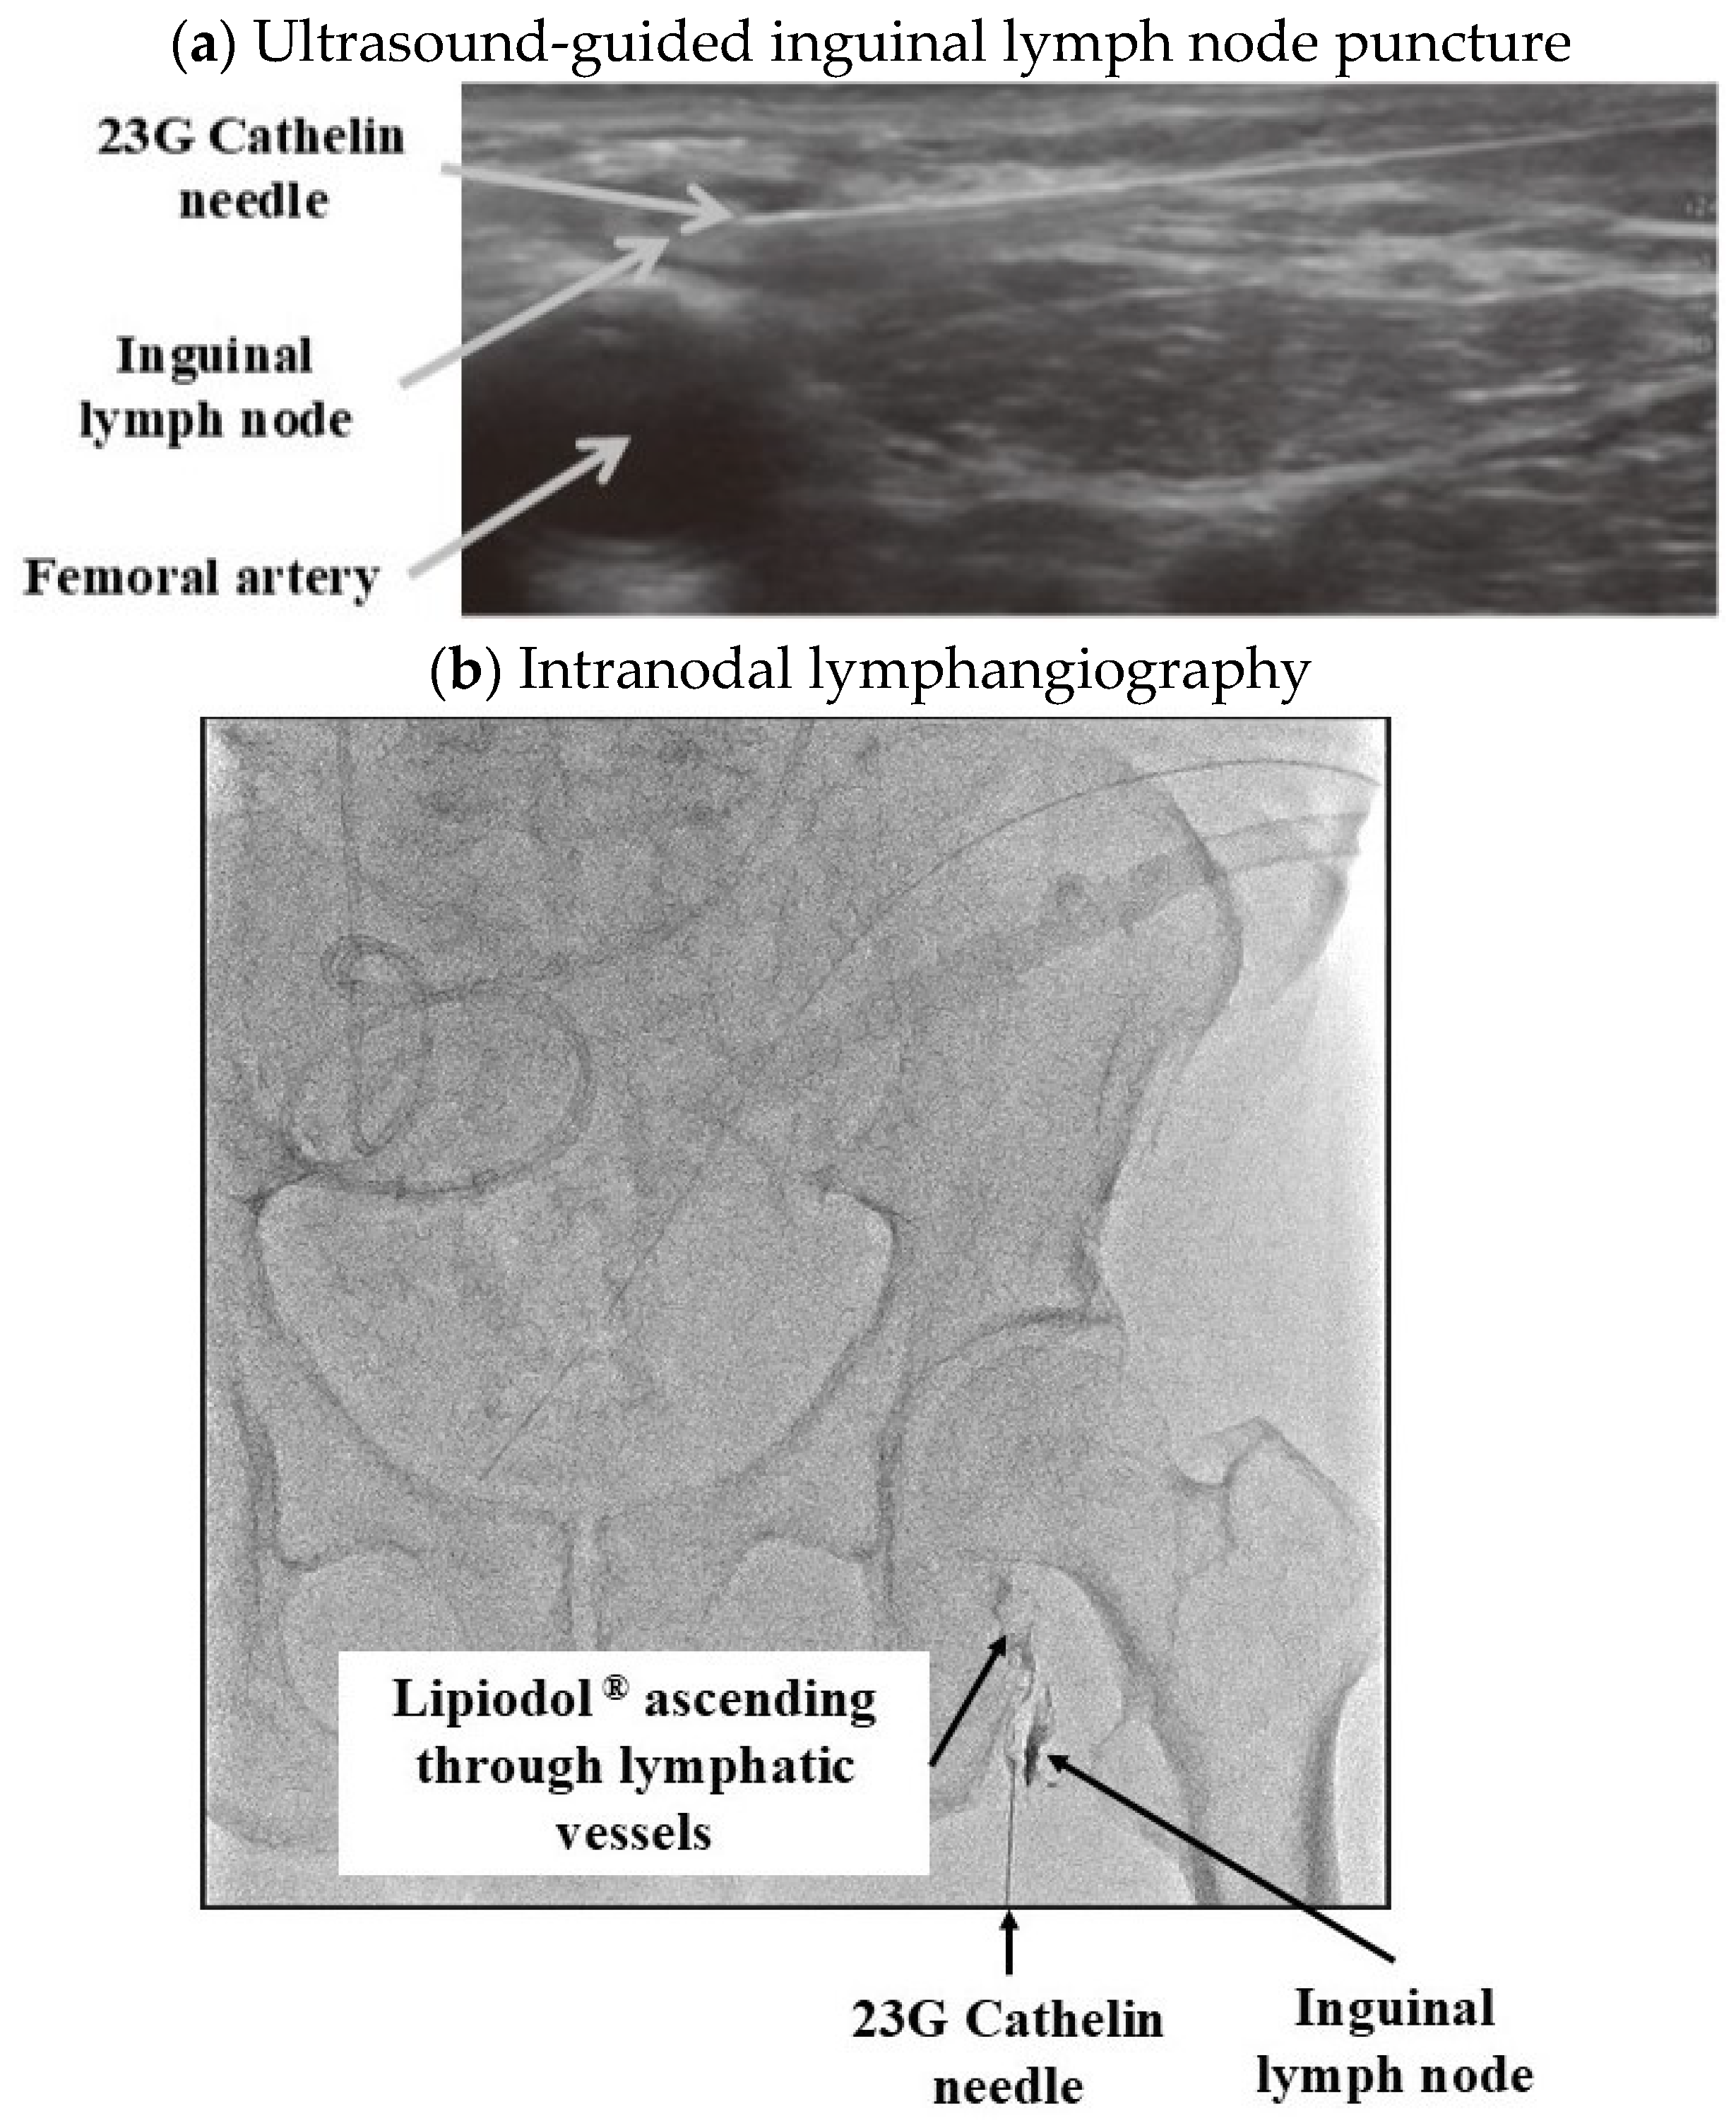

| 2. Lymphangiography, Embolization |

| · lipid-soluble iodinated contrast agent |

| · Embolization with NBCA (N-butyl-2-cyanoacrylate) |